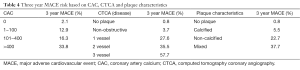

This ability of CTCA to visualize not only calcific but soft plaque and determine luminal narrowing possesses incremental prognostic value. Hou et al. used CAC, CTCA and plaque characteristics in a study of 5007 patients, of whom 363 developed MACE. They found the cumulative probability of 3-year MACE increased across CT strata for CACS, CTCA and plaque characteristics as shown in Table 4. The areas under the ROC curves were 0.72 using clinical markers, 0.82 (P<0.001) with the addition of CAC and 0.93 (P<0.001) with CTCA (21).

Full table